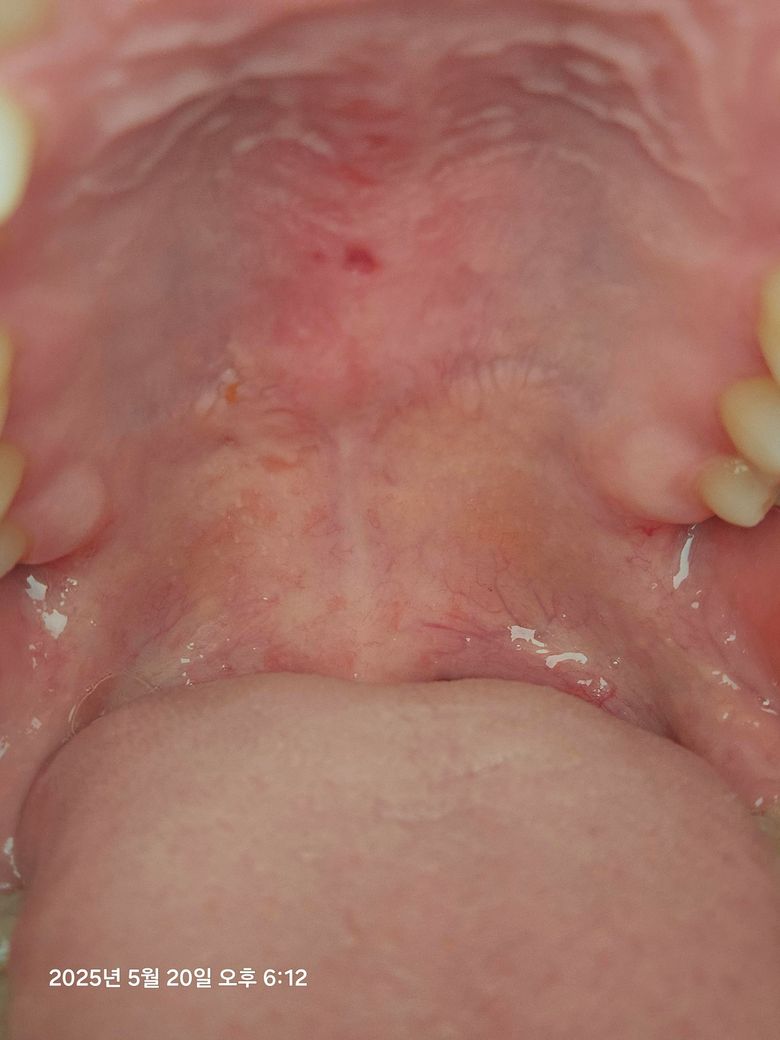

어느순간 밥먹을때 입천장이 쓰려서 혀로 더듬어보이 구멍처럼 느껴지더라구요.... 그냥 입천장이 까진거겠죠? 아님 혹시 다른 병일수도 있을까요?

입천장이 음식이나 다른 기구에 의해서 눌려서 생긴거 같습니다. 시간이 지나면 괜찮아 지실꺼에요.

어느순간 밥먹을때 입천장이 쓰려서 혀로 더듬어보이 구멍처럼 느껴지더라구요.... 그냥 입천장이 까진거겠죠? 아님 혹시 다른 병일수도 있을까요? -> 단순 상처로 보이긴 하나 바이러스나 세균 감염일 수도 있을 것 같습니다

현재 입안에 상처가 난 것으로 보이며 구내염으로 보입니다. 이 경우 너무 뜨겁고 까끄러운 음식은 피하는 것이 좋으며 미지근한 소금물로 소독을 하는 것이 회복에 도움이 됩니다